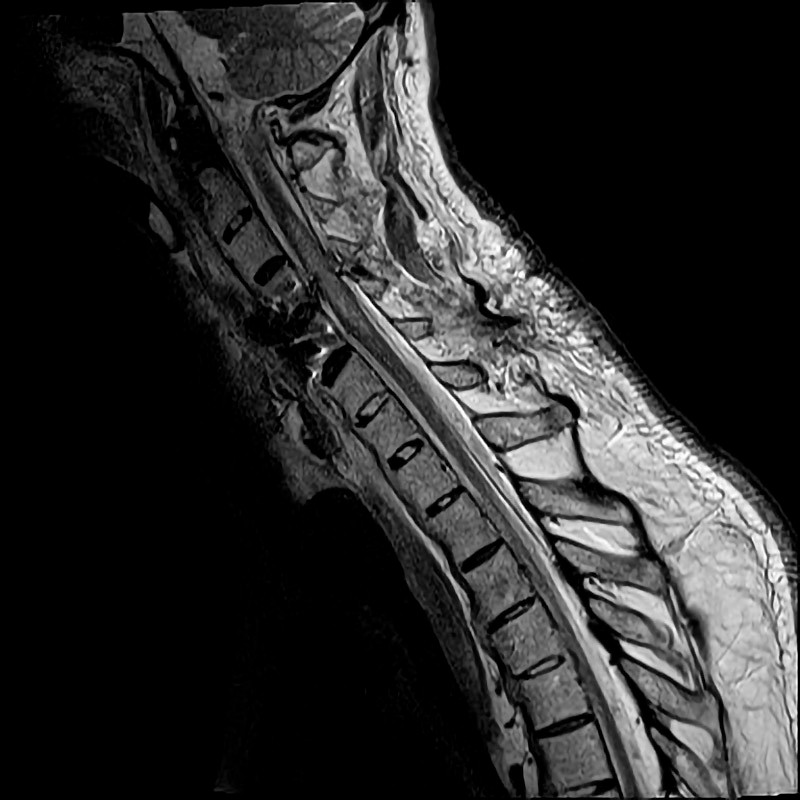

To måneder etter skaden ble pasienten på ny febril. Ved undersøkelse var han ikke orientert for tid. Han var ikke nakkestiv. Respiratorisk og sirkulatorisk var han uendret. Blodprøver viste CRP 91 mg/l, leukocytter 10,3 ∙ 109/l og nøytrofile granulocytter 7,5 ∙ 109/l. Urinstiks fra kateter viste utslag på leukocytter, nitritt og blod, og det ble startet peroral antibiotikabehandling mot antatt urinveisinfeksjon (trimetoprim-sulfametoksazol 160 mg/800 mg × 2). Blodprøver neste dag viste raskt stigende CRP på 219–261 mg/l. Undersøkelse av hjertet, lungene og abdomen viste igjen normale funn, bortsett fra at abdomen var utspilt og diffust trykkømt, men uten fokal trykkømhet, reflektorisk stramming eller bankeømhet over nyrelosjer. På mistanke om øvre urinveisinfeksjon ble det besluttet å bytte til intravenøs antibiotikabehandling (cefotaksim 2 g × 3). For å utelukke ny pneumoni ble det tatt røntgen thorax, som var normalt. Pasienten fremsto neste døgn økende delirisk med fallerende allmenntilstand. Vitale parametre var uendrete. Det var stigende CRP til 328 mg/l og forhøyete verdier av leukocytter på 13 ∙ 109/l og nøytrofile granulocytter på 10,4 ∙ 109/l. Verdiene av ALP, ASAT, GT og kreatinin var innenfor referanseområdet, mens bilirubin var lett forhøyet på 23 µmol/l (< 19 µmol/l). Mannen klaget over brennende smerter i alle ekstremiteter. Han hadde hatt tregere avføring enn vanlig, og det var synlig økt bukomfang, men uendrete funn ved undersøkelse av abdomen. Etter diskusjon i kollegiet valgte man nå å be om et umiddelbart kirurgisk tilsyn på grunn av mistanke om akutt abdomen. Kirurgisk vakthavende fant lett trykkømhet ved dyp palpasjon under høyre kostalbue og utspilt abdomen, men ingen kliniske tegn til peritonitt. Dette var nokså sparsomme kliniske funn, men man valgte å henvise pasienten til CT abdomen på mistanke om abdominalt infeksjonsfokus, spesielt i galleveier. CT-undersøkelsen viste galleblære med gallesten og fortykket vegg forenlig med galleblærebetennelse (figur 2). Det ble startet behandling av galleblærebetennelsen med piperacillin/tazobaktam intravenøst samt perkutan drenasje via galleblæredren, hvor det tømte seg gult puss. Behandlingen ga rask klinisk og laboratoriemessig bedring.

Ultralyd av abdomen ville vært en målrettet primærundersøkelse ved spørsmål om gallesten og galleblærebetennelse. Når CT abdomen ble valgt som primære undersøkelsesmetode, tyder det på et uklart klinisk inntrykk og et behov for å utelukke flere tilstander samtidig med rask bildediagnostikk.